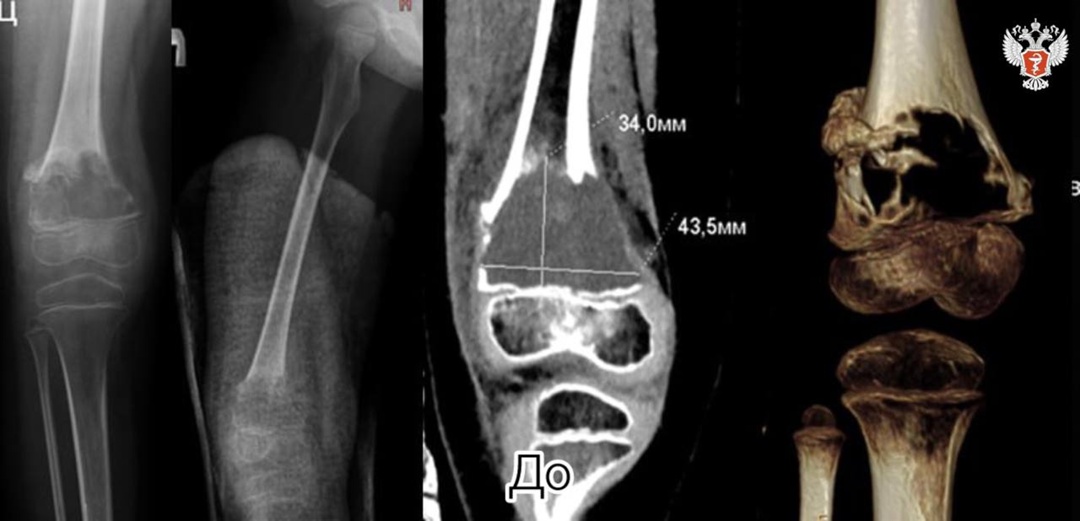

При данной патологии здоровая кость истончается, меняется ее структура, это приводит к патологическим переломам. У пациентки киста выросла размером со спичечный коробок (34,0 мм * 43,5 мм). Произошел перелом бедренной кости.

— Ни одной кортикальной пластинки не было, киста буквально съела тот фрагмент бедренной кости, где располагалась. Совсем близко находилась зона роста, и любое промедление грозило еще более серьезными осложнениями, — рассказал заведующий отделением №6 НМИЦ травматологии и ортопедии им. ак. Г.А. Илизарова Минздрава России Сергей Леончук.